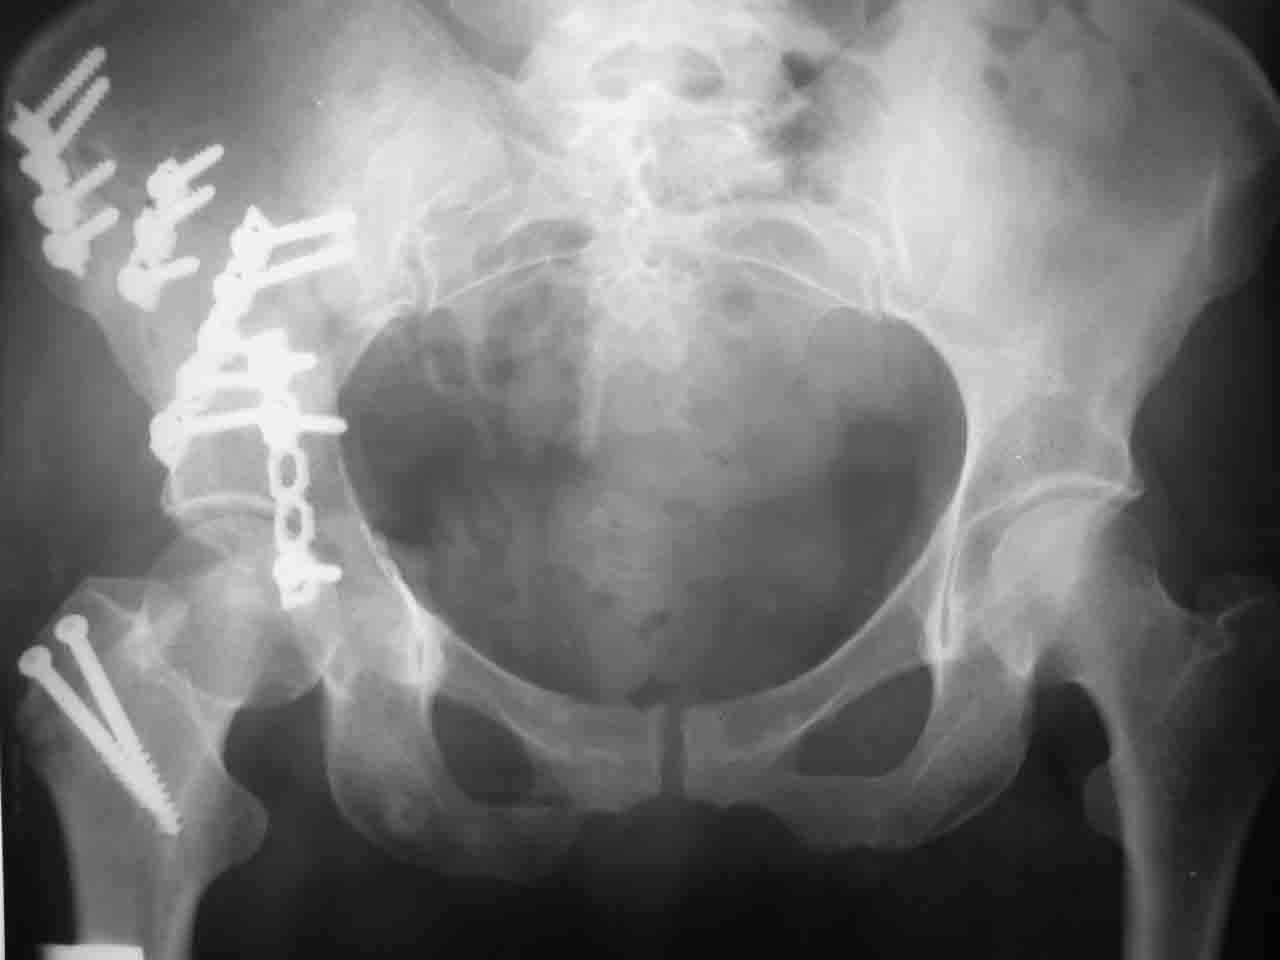

Интерес к реконструкции вертлужной впадины у меня появился довольно-таки давно, но до недавнего времени как-то не ощущалась готовность к практической реализации, а местный подход достаточно консервативен - перелом срастется,

а далее будет видно. Такую точку зрения я не разделяю, поэтому через конференции,ортофорум и свои случаи пытаюсь практически и теоретически *продвинуть* для себя тему реконструкции вертлужной впадины.

Логика подсказывает, что все-таки лучше иметь анатомически полноценную впадину, хотя ранее упоминалось состояние вторичной конгруэнтности и одно наблюдение у меня есть, когда у больного с полностью нарушенной анатомией впадины и подвывихом головки бедра кзади и кверху боли отсутствовали при относительно достаточном для стиля жизни больного объёме движений. Но это только одно наблюдение и кроме перелома впадины у этогобольного была и тяжелая ЧМТ в анамнезе. Основываясь на формулировке структуры ацетабулюм Э. Летурнеля - как перевернутой буквы Y, впадина для полноценной функции сустава должна иметь сферичность, соответствующую размеру головки бедра и если один из компонентов в дефиците, то функциональные последствия рано или поздно проявятся.

Сложностью, ассоциативностью характера перелома, я бы с радостью воспользовался мининвазивной перкутанной фиксацией винтами, но боюсь, что результат был бы ещё хуже, техникой непрямой репозиции перелома не владею, поэтому пытаясь получить анатомичную впадину приходится широко открывать, по крайней мере пока, а дальше буду пытаться уменьшать пространство...

Илеофеморальный доступ не совсем передний и сравнительно с илеоингвинальным, и Кохера-Лангенбека открывает весь наружный таз кроме самых передних отделов лонных костей, фиксацию которых я не ставил в задачу. Обширность диссекции, большая длительность операции и более высокий риск гетерооссификации - отрицательные моменты в обмен на возможность легче ориентироваться.

Вопрос доступа к вертлужной впадине при остеосинтезе задача не простая. Конечно, у Летурнеля и Тайла всё давно описано, нам остается только брать на вооружение. Но сами понимаете, что не бывает двух одинаковых ситуаций, поэтому в каждом случае вопрос решается сугубо индивидуально. Наша главная цель - восстановить анатомию с нанесением минимальной дополнительной травмы тазобедреннному суставу, думаю с этим никто не поспорит. Расширенный илиофеморальный доступ уж слишком травматичен (как сказал один коллега "таз лежит отдельно, больной отдельно").Стоит ли делать из пациента анатомический препарат для того чтобы легче ориентироваться. Да и нужно ли собирать всю "мозаику"? Мы применяли при таких операциях своеобразную операционную хитрость - сначала устраняли грубое смещение крыла под гребнем с фиксацией так называемой "плавающей" пластиной (временно фиксированной на двух винтах)- доступ или продлевали боковой, или делали небольшой дополнительный разрез над гребнем. Это позволяло устранить грубое смещение и захождение отломков тела повздошной кости, что значительно облегчало репозицию и остеосинтез впадины над сводом. Основное внимание конечно же уделяли нагружаемому задне-верхнему отделу. Сообщите ваш адрес, пришлю схемы и рентгенограммы.